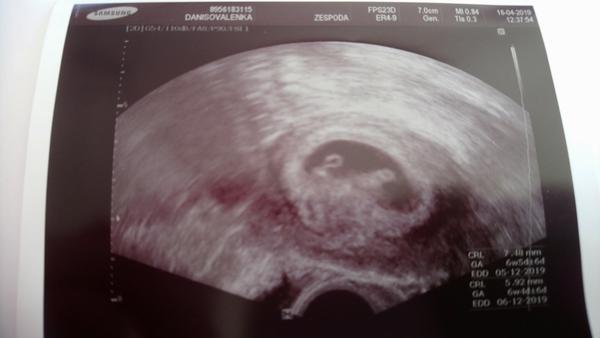

Termín porodu listopad/prosinec 2019